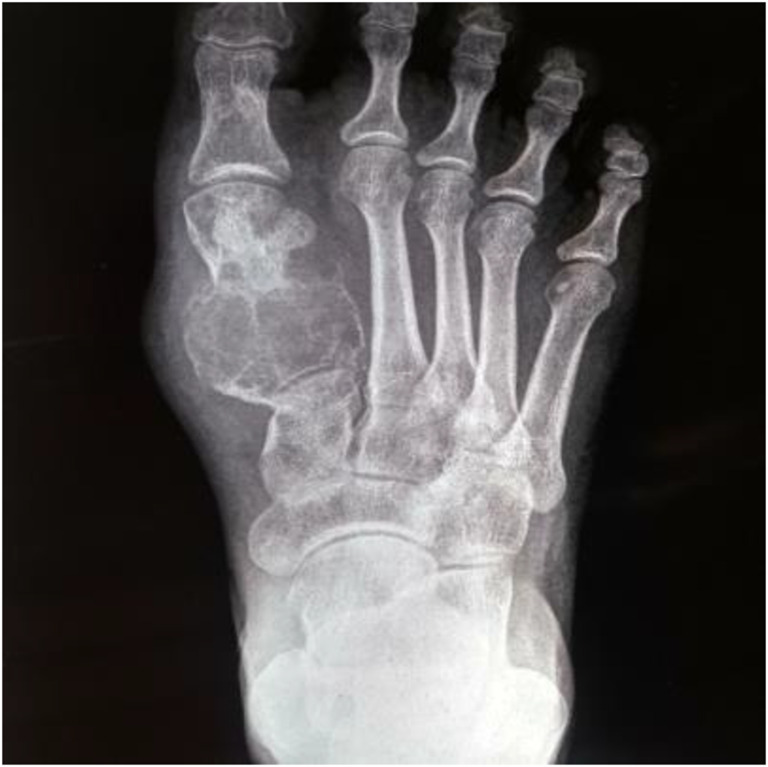

Twenty-nine-year-old female with no known comorbidities, Eastern cooperative oncology group(ECOG) score 1 came with chief complaint of foot swelling for 6 months. Patient has history of trauma later which she noted swelling. Initially evaluated at local hospital and was later referred to Dr. B. Borooah cancer institute. On examination there was around 5 × 6 cm swelling on dorsum or right foot at first metatarsal area. Blood work up was with in normal limits except for serum alkaline phosphatase (206 u/l). X-ray right food was suggestive of expansile, lytic, destructive lesion of first metatarsal. Magnetic resonance imaging of lower limb was suggestive of approximately 5 × 3 cm lobulated T2 hyperintense lesion involving the first metatarsal shaft proximally, with cortical destruction with sparing of distal metatarsal. 99mTc-methylene diphosphate (MDP) whole body scan was suggestive of increased osteoblastic activity in first right metatarsal with uptake nowhere else. Contrast-enhanced computerised tomography of chest and abdomen was normal. Core biopsy was suggestive of low-grade osteosarcoma. Doppler of bilateral lower limbs was with in normal limits (Figs. 1 and 2).

Fig. 1.

X-ray image of tumour